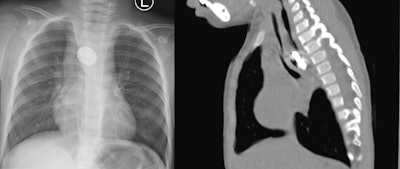

Posteroanterior chest x-ray and sagittal view of the thoracic CT revealing a foreign body in the thoracic esophagus. Image courtesy of the International Journal of Surgery Case Reports through CC BY 4.0.A chest x-ray revealed a halo sign and a thoracic CT scan showed a round object obstructing her esophagus. Attempts to visualize and retrieve the foreign body endoscopically were unsuccessful, and the surgeons performed a thoracotomy to retrieve it.